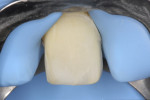

Glass-ionomer cement was used as a temporary material. The patient was also informed about the increased risk for fracture, which can occur between bleaching appointments. She was advised to avoid eating hard foods and chew with caution. The bleaching agent was re-placed at 7 and 14 days after the first appointment. Three rounds of sodium perborate treatment produced satisfactory color improvement (Figure 11).

Because of the remarkably good result of the nonvital bleaching (Figure 12), a decision regarding tooth preparation versus indirect restoration fabrication was unnecessary at that time.